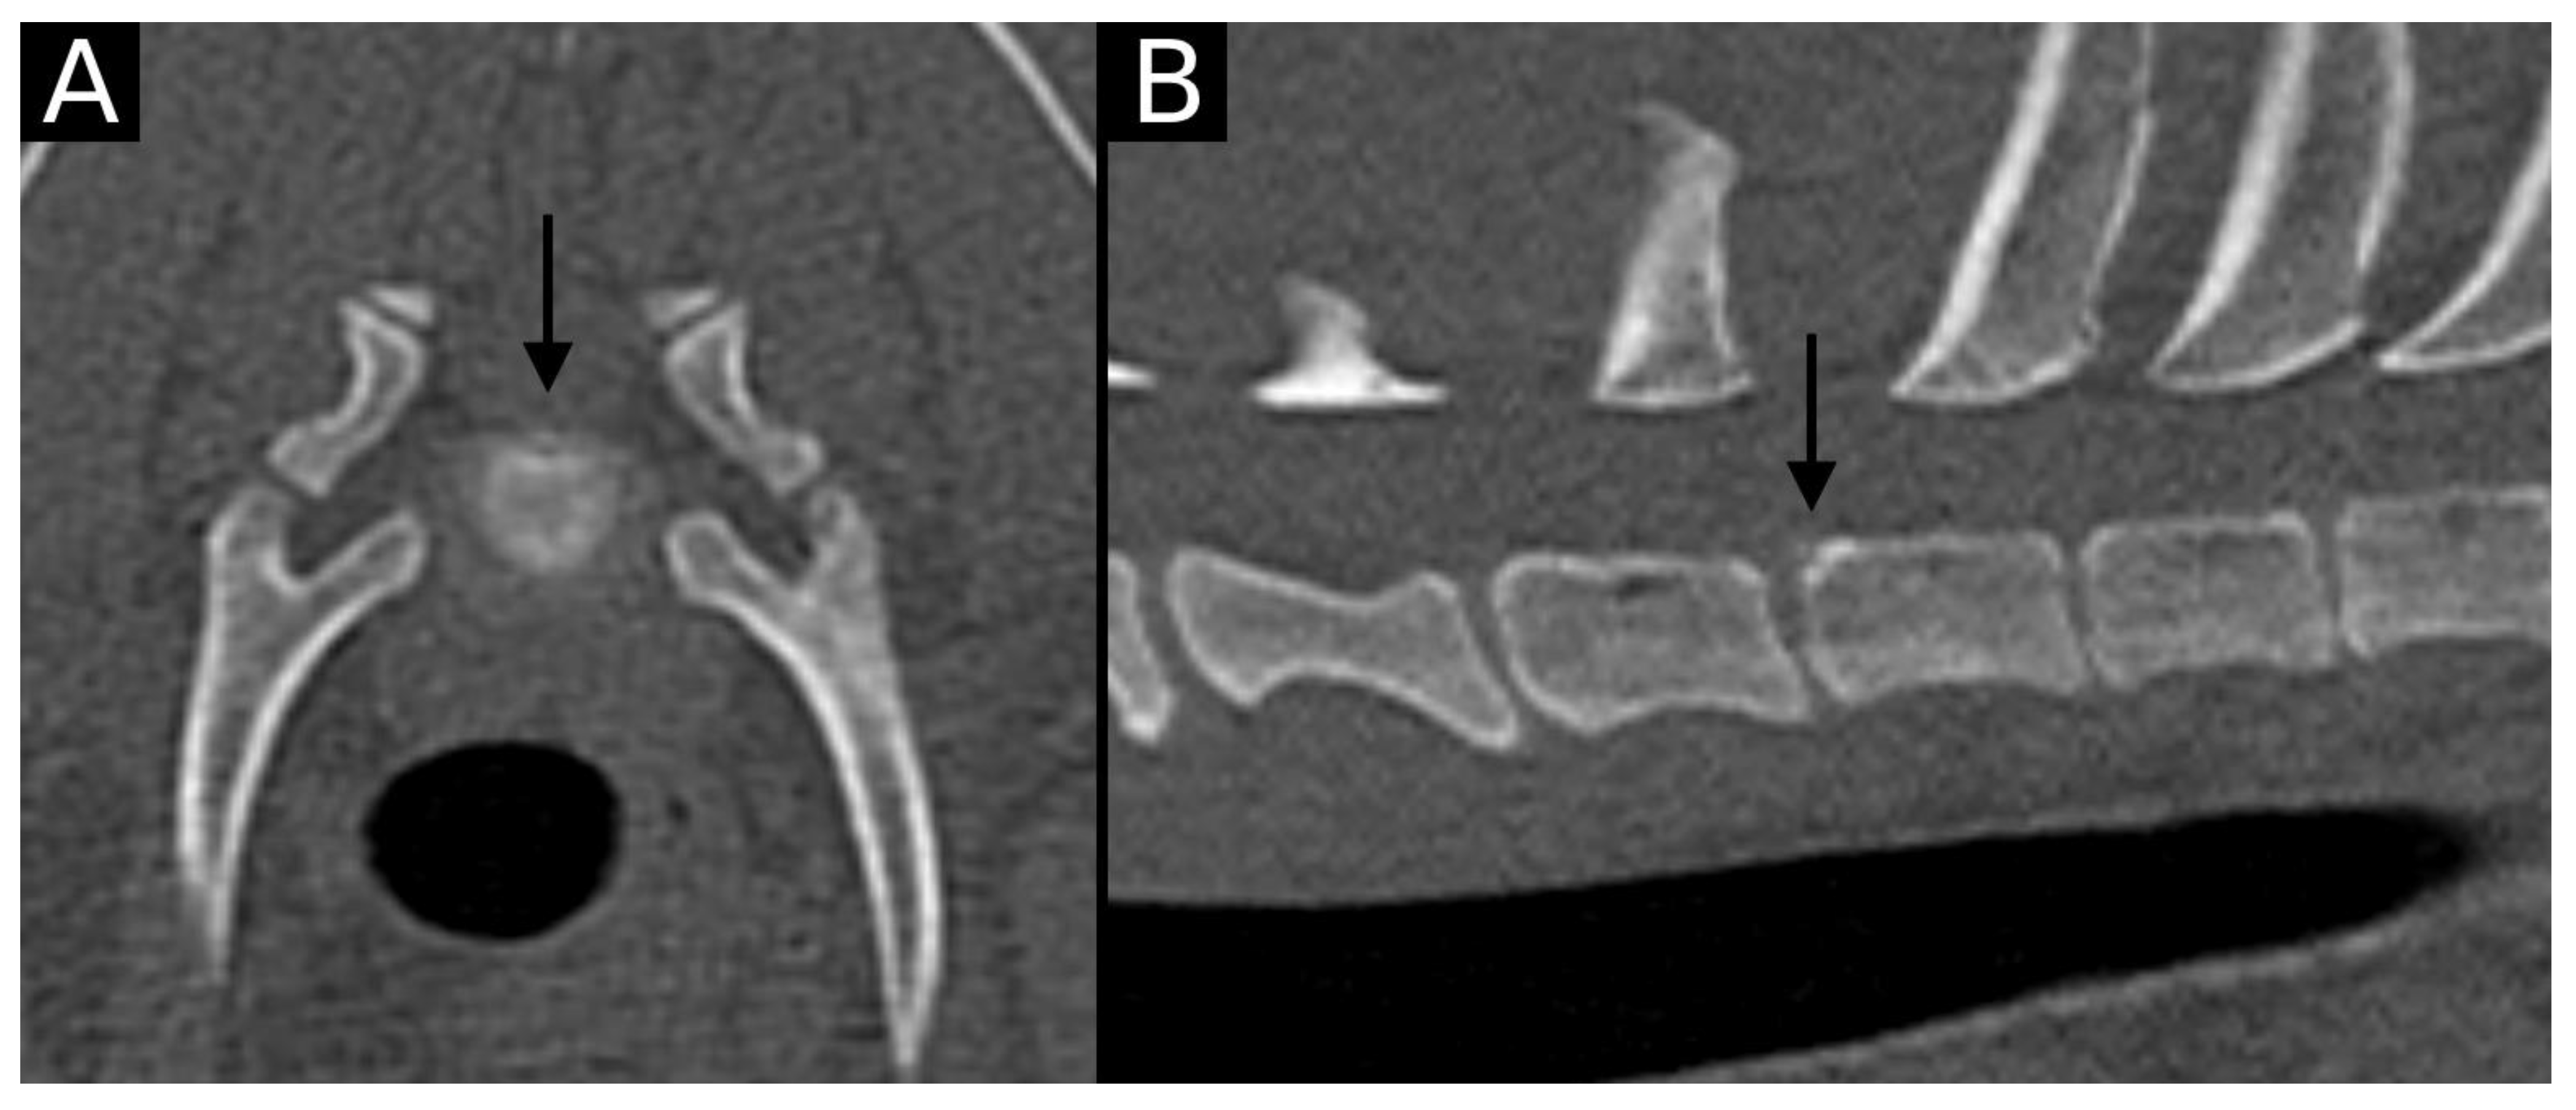

The junction between the endplates and intervertebral discs of the cervicothoracic junction (C6–C7, C7–T1 and T1–T2) were evaluated for the presence of alterations. When present, they were also graded and scored for EPJA, IVD herniation, spondylosis deformans, endplate sclerosis, articular process joint osteoarthrosis, and the presence of vertebral morphological abnormalities. The scoring system for endplate junction alterations and other spinal abnormalities was based on the proposed scoring by Tellegen et al. [13] for presumed EPJF at the lumbosacral spine. Endplate junction alterations were classified into four types (A, B, C, D): Type A involved presence of irregularity of the endplate margins without an obvious free fragment (Figure 1 and Figure 2); Type B involved avulsion evidenced by a thin rim of bone associated with a defect in the dorsal edge of the adjacent endplate (Figure 3); Type C included frank avulsion of a bony fragment (Figure 4) and Type D included presence of bony avulsion of both endplates. If EPJA was present, location (dorsal or ventral) and lateralization of the defect were also recorded. IVD herniation was graded from grades 0 to 3: grade 0 indicated no to mild (0–24%) herniation; grade 1 indicated mild to moderate (25–49%) herniation; grade 2 indicated moderate to marked (50–74%) herniation; grade 3 indicated marked herniation to complete obliteration (75–100%) of the vertebral canal by disc material. Spondylosis deformans was scored from grades 0 to 3: grade 0 indicated no enthesophytes; grade 1 indicated a small enthesophyte at the edge of the epiphysis that does not extend past the endplate; grade 2 indicated the presence of an enthesophyte that extends beyond the endplate but does not connect to the adjacent vertebra; and grade 3 indicated connecting enthesophytes from adjacent vertebrae forming a mineralized bridge. The other mentioned abnormalities (IVD mineralization, endplate sclerosis and articular process joint osteoarthrosis) were scored as present (1) or absent (0).

Figure 1. Transverse (A) and sagittal (B) reconstructions in bone algorithm. An irregular contour surrounded by mild sclerosis (arrow) is observed at the ventral aspect of the C6 caudal endplate, consistent with EPJA Type A. Mild spondylosis deformans is observed in the same vertebra.